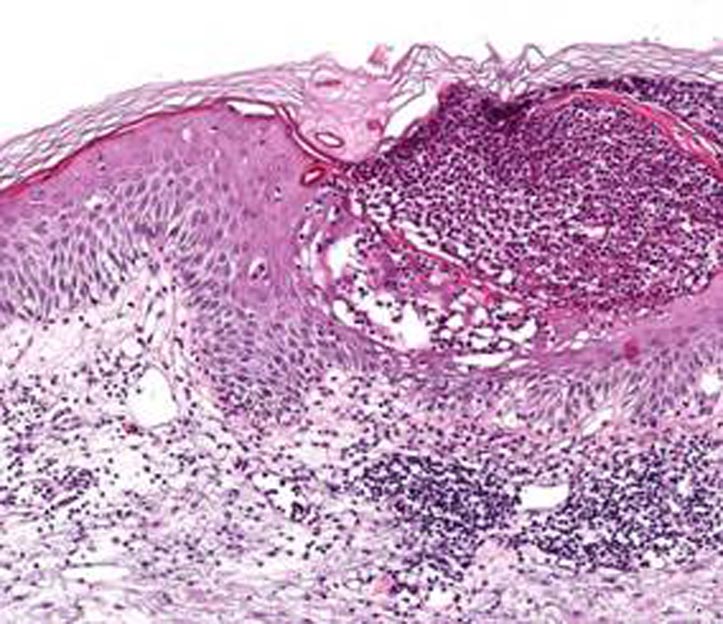

Fig 2: Histopathological examination showing subcorneal pustule with neutrophils and spongiosis (H&E stain, 40x).